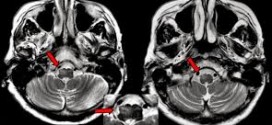

La Adrenoleucodistrofia por lo regular se trasmite de padres a hijos como un rasgo genético ligado al cromosoma X. Por lo tanto, afecta sobre todo a los hombres, aunque algunas mujeres portadoras pueden tener formas más leves de la enfermedad. Es una enfermedad genética ligada al cromosoma X que puede comenzar en la infancia, en la adolescencia o en la …

Leer Más